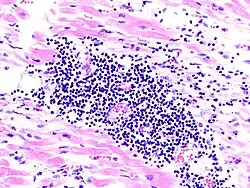

Virale Myokarditis

Ät.: Coxsackie-, ECHO-, Adenoviren, Influenzaviren

Pathogenese: Herzmuskelnekrose durch Virus und T-Zell-vermittelte Immunreaktion.

Mikro: Interstitielles lymphozytäres Infiltrat (kleine blaue Zellen), kaum Nekrosen.